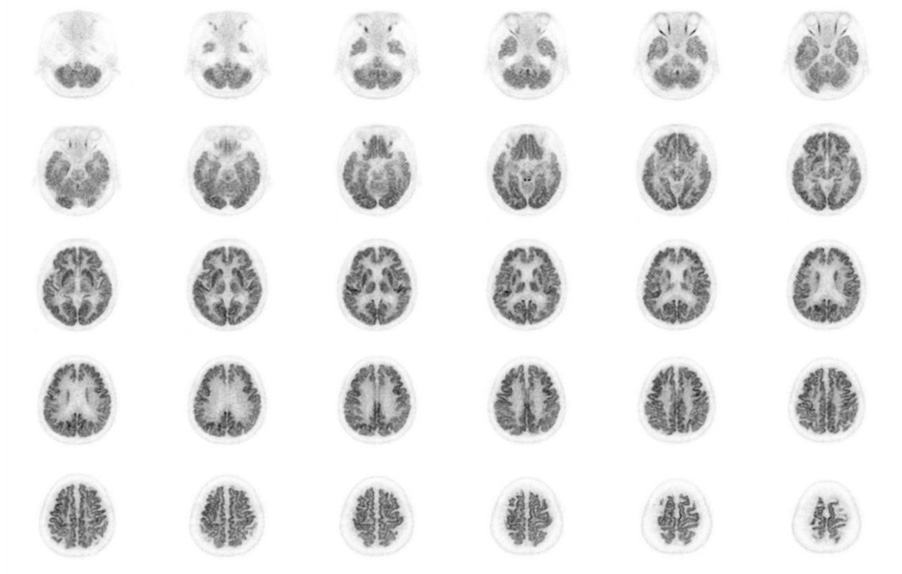

Head / Case3 : FDG

Axial

Courtesy : Kindai University Hospital

- Imaging protocol

- Injected dose: 4.49 MBq/kg, 18F-FDG

- Uptake time: 46 minutes

- Scan time: 30 minutes